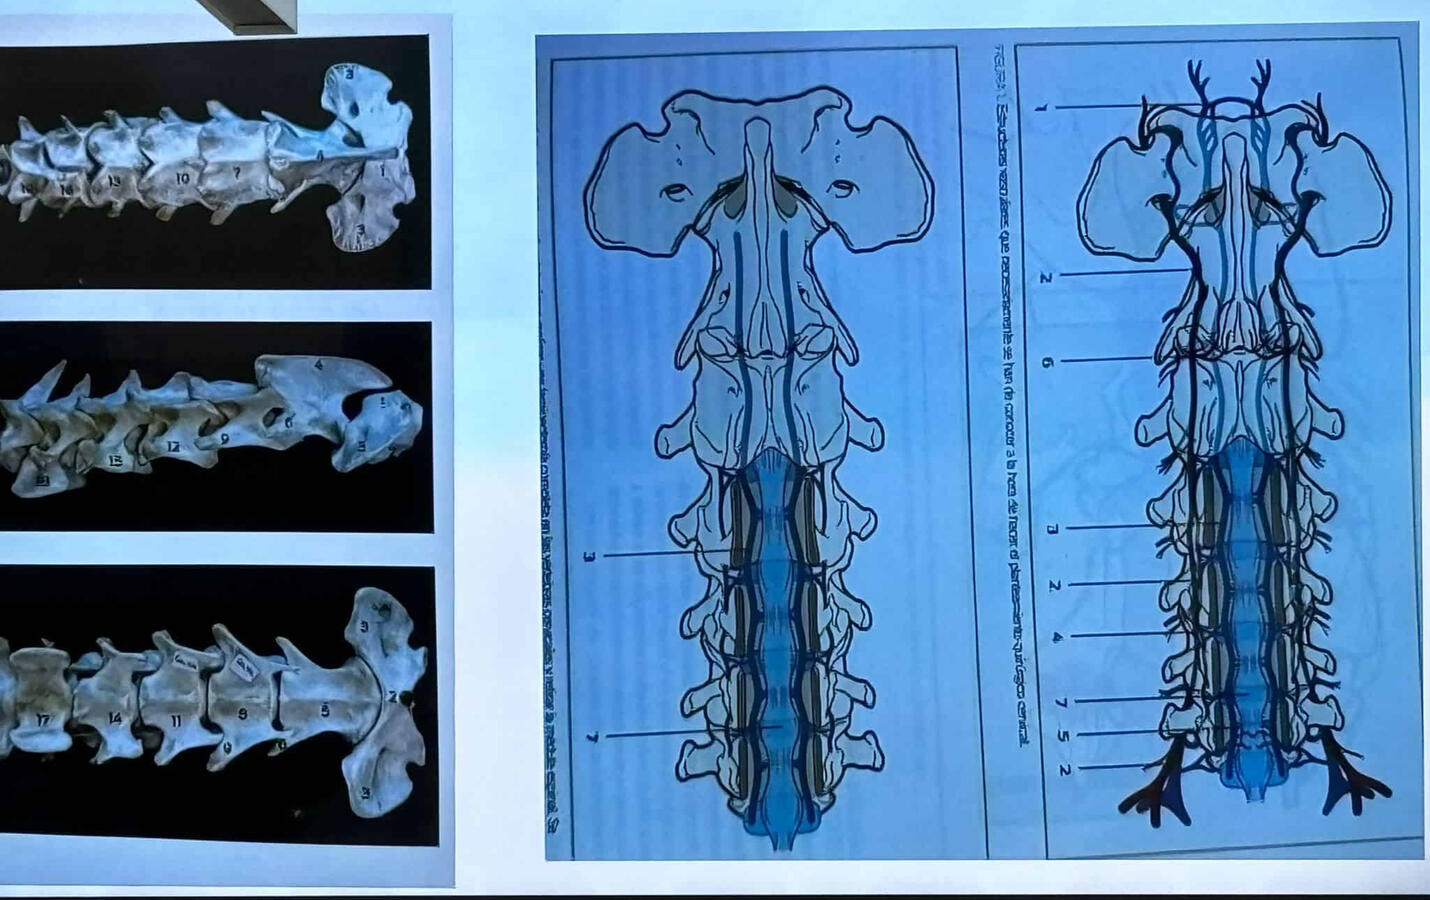

24 years of experience as a veterinarian, specializing in surgery and anesthesia. A member from the very beginning of the emergency veterinary team - a unique body in the world - coordinated with Cruz Roja, and El Cabildo de Tenerife. Collaborator for 18 years with over 15 Animal Protection Associations, such as ASFA, K9 Chafiras Tenerife, Burros Felices de El Hierro, Verein Hilfe Fur Tiere, Pro Animal Gomera, the club de la huella... Among others.

About Dr. Cesar Bertoldi

After my academic studies, I worked for 6 years as the head of residents at the MAC (Medicine Animal Córdoba) veterinary hospital, in charge of the anesthesia and pain control department.

In addition, I continuously train in the areas of orthopedics, traumatology, and pain control. General and traumatological surgery.